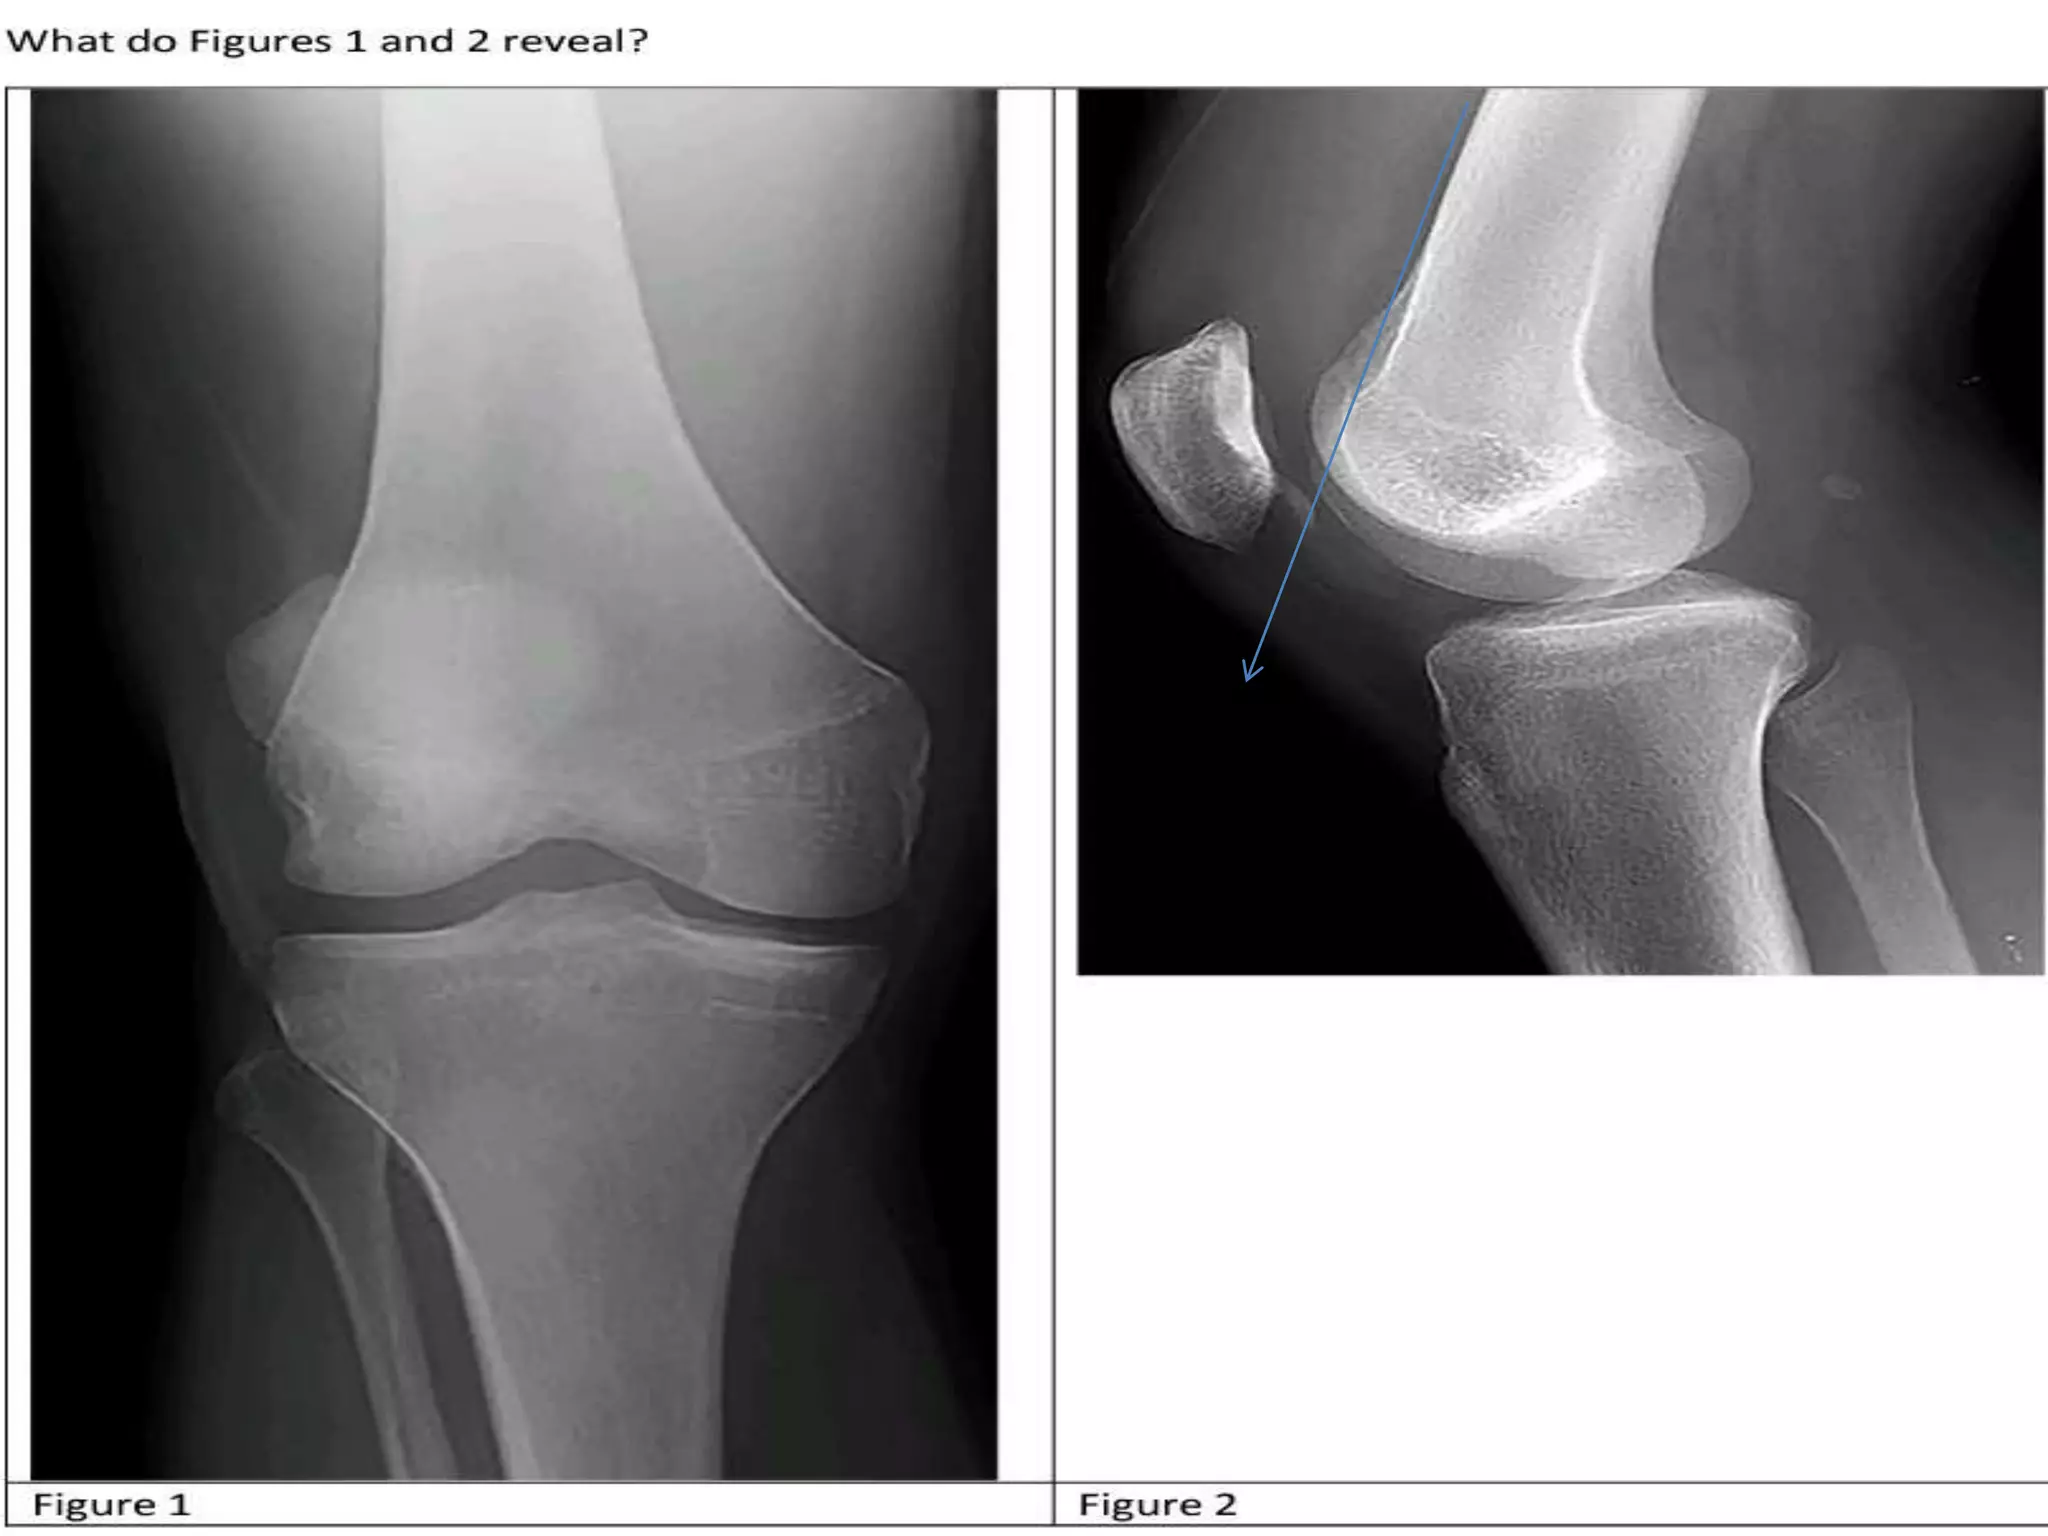

• B. An osseous or osteochondral loose

fragment

An osseous or osteochondral loose

A patella nondisplaced fracture

• There is no oblivious patella fracture in the given x-

ray image